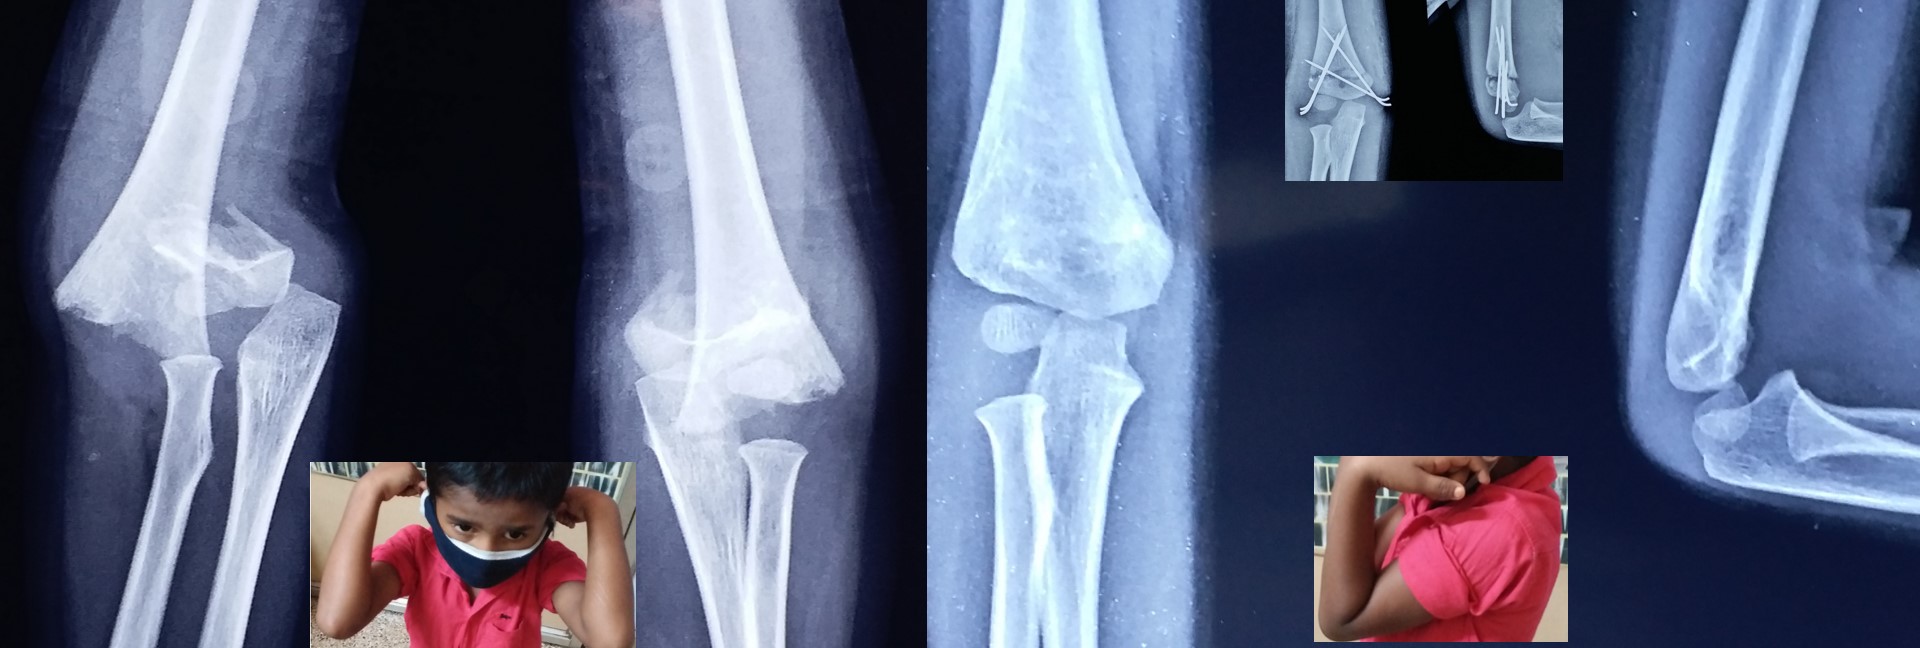

CRPP ( Closed Reduction Percutaneous Pinning )

• It can be applied to diaphyseal region adjacent to metaphysis in pediatric fractures, especially distal 3rd arm, forearm and leg fractures.

• Almost all complications of open surgeries can be avoided by CRPP with very minimal complications.